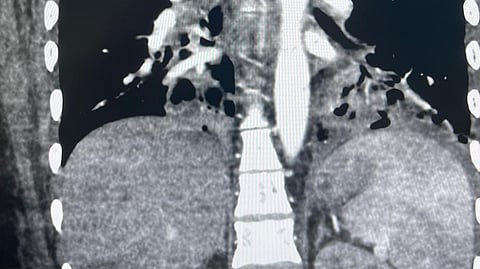

سجّل فريق الأشعة التداخلية في مجمع الملك فيصل الطبي، التابع لتجمع الطائف الصحي، إنجازًا طبيًا نوعيًا بعد نجاحه في إجراء عملية إصمام الشريان القصبي (Bronchial Artery Embolization) لمريضة كانت ترقد في قسم العناية المركزة وتعاني من نزيف رئوي حاد تجاوزت كمية الدم المفقودة فيه 90 مل يوميًا، بالإضافة إلى إصابتها بالتهاب رئوي حاد.

ونفّذ الفريق الطبي الإجراء عبر إدخال القسطرة عن طريق الشريان الفخذي وتوجيهها بدقة إلى الشرايين المغذية لمصدر النزيف، حيث تم استخدام مواد طبية متخصصة لإغلاق تلك الشرايين بنجاح، ما أدى إلى توقف النزيف وتحسن ملحوظ في حالة المريضة، دون تسجيل أي مضاعفات.